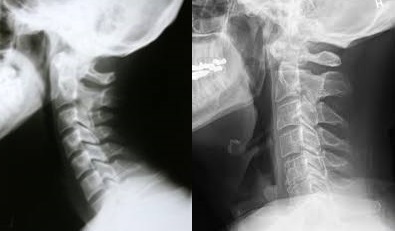

거북목 증후군이란 옆에서 봤을 때 완곡한 C자 형태를 갖추고 귀와 어깨의 라인이 일직선상에 위치한 정상적인 상태가 아니라, 거북이처럼 머리와 목이 길게 빼져 있거나 목 커브가 없어져 일자 모양을 보이는 것을 말한다. 일자목이라고도 한다.

이를 방치할 경우 경추 통증의 원인이 됨에 따라 목·어깨의 통증과 함께 두통이 따르거나, 척추나 턱 관절 등에도 영향을 미치게 된다. 성장기에 내버려 두면 신체 발육의 저하, 집중력 약화 및 정서적 악영향이 우려된다. 또 성인이 돼도 두통, 손 저림, 어깨통증 등의 만성통증으로 도질 수 있어 주의를 요한다. 이를 예방하려면 평소 바른 자세를 유지하려고 노력하거나 잠을 잘 때 목의 C자형을 유지할 수 있는 베개를 선택해야 한다.

목 경추의 곡선을 자연스럽게 유지해주면서 거북목 증후군·목 디스크 예방에 도움을 주는 티베개는 목 부위에 압박을 가하지 않고 후두골 하단부를 양손으로 받쳐주는 듯한 구조로 C자목을 형성하여 잠자는 자세를 올바르게 해주고 기도를 확보해준다. 바른 자세로 자야 건강을 향상시킬 수 있다. 따라서 티베개는 자주 목이 결리거나 뻐근한 어깨로 고생하는 사람들에게 필요하다.